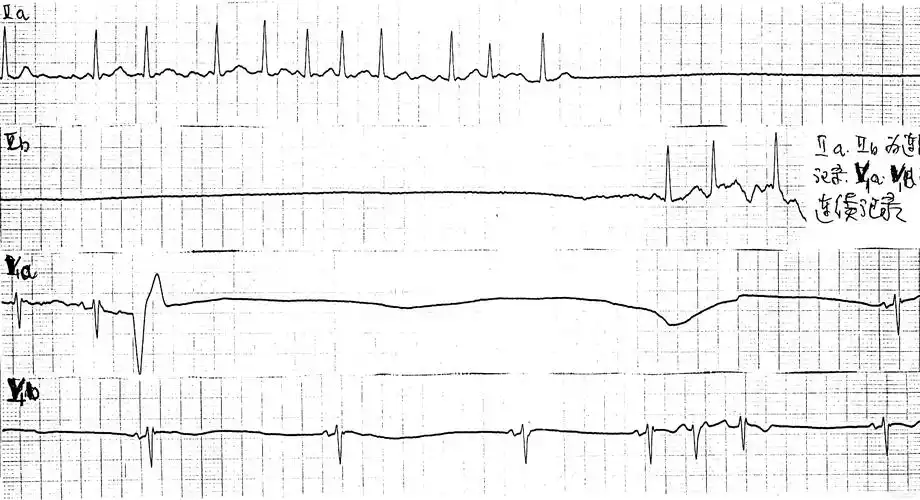

4,心室自身节律(即心电机械分离):心室肌呈慢而微弱的收缩(20~30次

三,心搏骤停的心电图表现 心脏停搏 电机械分离 室颤:qrs-t波群消失

电机械分离

房室分离 - 心电图脑电图专业讨论版 - 爱爱医医学论坛